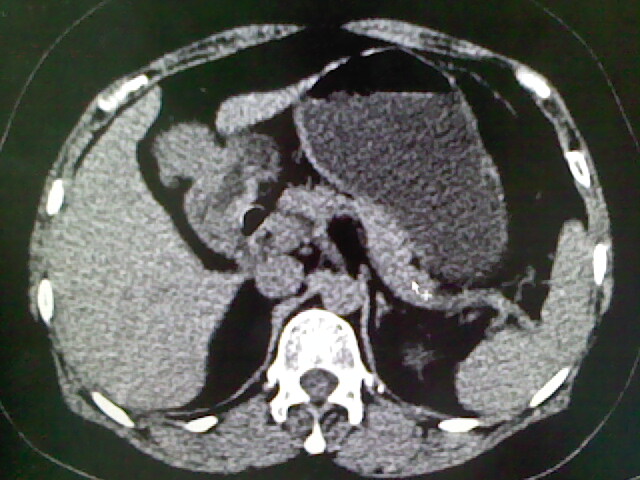

以下是引用卜一在2009-4-2 13:26:00的发言:[br]胆囊颈部结石伴胆囊炎!另:建议增强,待除外肝内占位及胆囊占位!

以下是引用liaoqiang在2009-4-2 16:23:00的发言:[br]胆囊是否切除?胆囊颈区致密影考虑金属夹?结石?肝脏右叶低密度影,考虑增强。